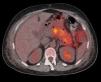

Pancreatitis aguda como síntoma inicial de un tumor de célula pequeña pulmonar

Acute pancreatitis as an initial symptom of a small-cell carcinoma of the lung